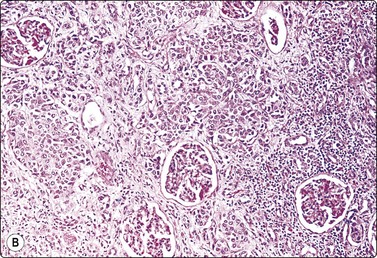

Wilms’ tumor (Figs 12.27 and 12.28)103-105

image

Fig. 12.27 Wilms’ tumor

Biphasic tumor; cohesive tubular structure and undifferentiated mesenchymal cells (MGG, HP).

Fig. 12.28 Wilms’ tumor

Small round cell tumor pattern of undifferentiated blastema (A, MGG; B, Pap, HP).

Criteria for diagnosis

Numerous undifferentiated small cells, single and in tight clusters (blastema),

Small, round or ovoid, hyperchromatic nuclei; multiple small nucleoli,

Scanty cytoplasm,

Epithelial differentiation: rosettes, tubular structures or cords (commonly present),

Mesenchymal differentiation: spindle cells (sometimes present).

Wilms’ tumor (nephroblastoma) is predominantly a tumor of childhood and is dealt with in more detail in Chapter 17. However, it can also occur in adults. Smears are usually dominated by small, undifferentiated malignant cells representing blastema. A specific diagnosis requires in addition evidence of epithelial and mesenchymal differentiation, but this may only be obvious in the better-differentiated tumors. Individual cells generally appear undifferentiated. Epithelial differentiation is suggested by microarchitectural patterns such as rosettes, tubules or cords (Fig. 12.27), which are not always present in smears. Correlation with clinical and radiological findings is important. The diagnosis may be supported by ancillary studies. The results of immunostaining are variable, depending on differentiation. Useful markers are vimentin, LMWCK, EMA and WT1. Heterogeneous cytogenetic abnormalities can be demonstrated in a proportion of tumors.